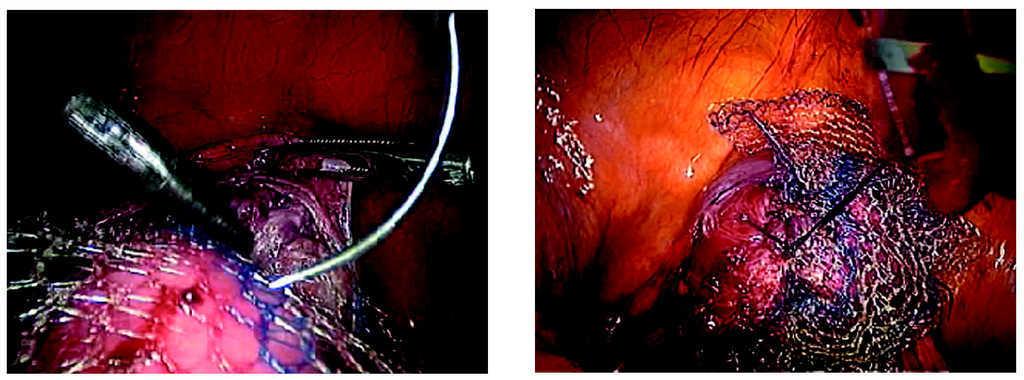

-- Paso cuarto. Colocación de 2 piezas rectangulares de malla de polipropileno (Gynemesh; Ethicon Inc. Somerville, NJ) en forma de Y sobre las caras anterior y posterior de la vagina (figs. 14-17).

Figuras 14 y 15. Fijación de la malla con puntos endoscópicos con sutura no reabsorbible sobre el músculo pubococcígeo.

Figuras 16 y 17. Fijación de la malla con puntos endoscópicos con sutura no reabsorbible sobre la fascia vaginal en su cara anterior y posterior.

-- Paso quinto. Fijación de la malla con puntos endoscópicos con sutura no reabsorbible sobre el promontorio del sacro (figs. 18 y 19).

Figuras 18 y 19.Detalle de la fijación de la malla al sacro.